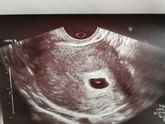

20Дпп на УЗИ 1ПЯ6 августа 2019 10:15 20дпп на УЗИ 1ПЯ 16мм, ЖМ 4мм.. 4/5 недель? Мой долгожданный, останься пожалуйста со мной???